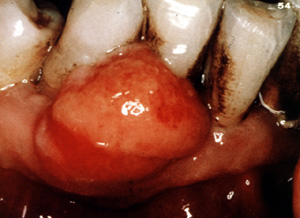

Esta imagen

ilustra bien cómo estas lesiones pueden crecer sin tratamiento. El

hueso subyacente puede ser reabsorbido.